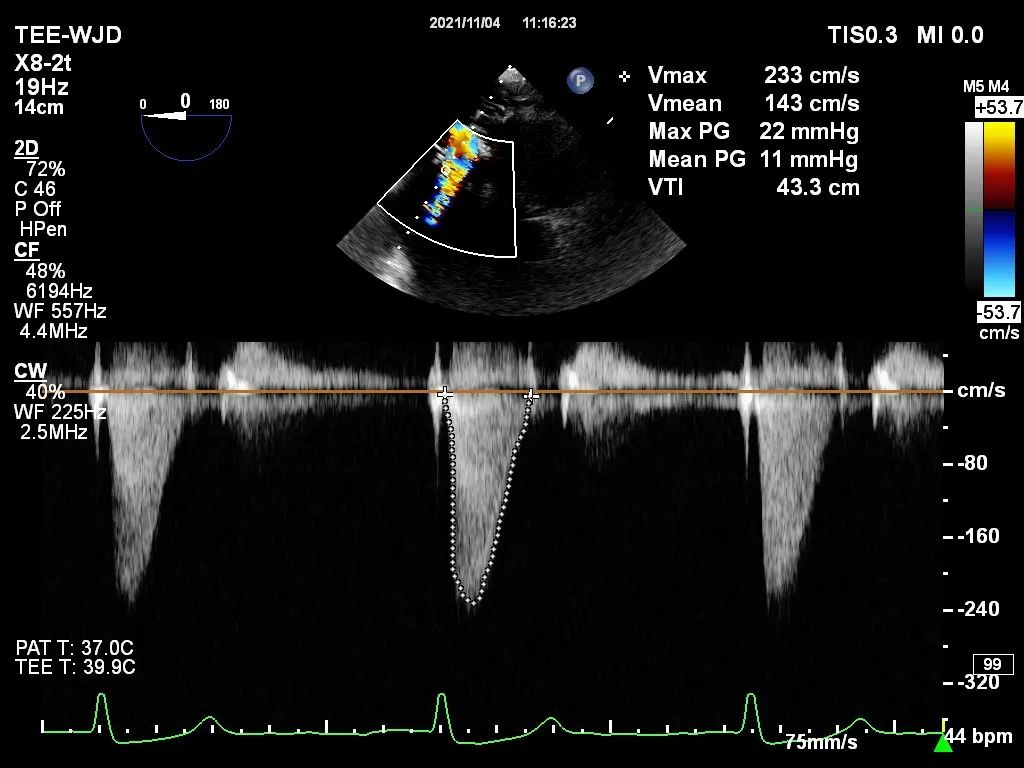

近日,中国医学科学院阜外医院潘湘斌教授团队,在多科室的通力配合下,凭借扎实的手术功底顺利完成一例经导管主动脉瓣和二尖瓣瓣中瓣置换术。

诊断:二尖瓣生物瓣置换术后,二尖瓣重度狭窄;主动脉瓣生物瓣置换术后,主动脉瓣中重度狭窄;三尖瓣成形术后,三尖瓣中度关闭不全;心房颤动;肺动脉高压;高血压2级(极高危)。

手术过程